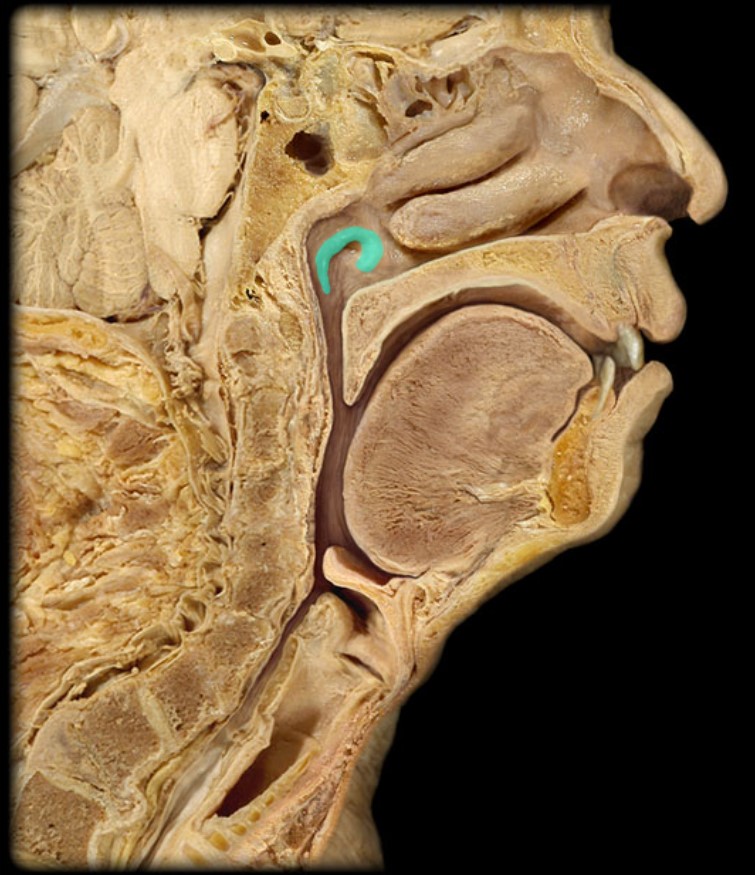

Inferior Nasal Concha

25

New cards

Middle Nasal Concha

26

New cards

Superior Nasal Concha

27